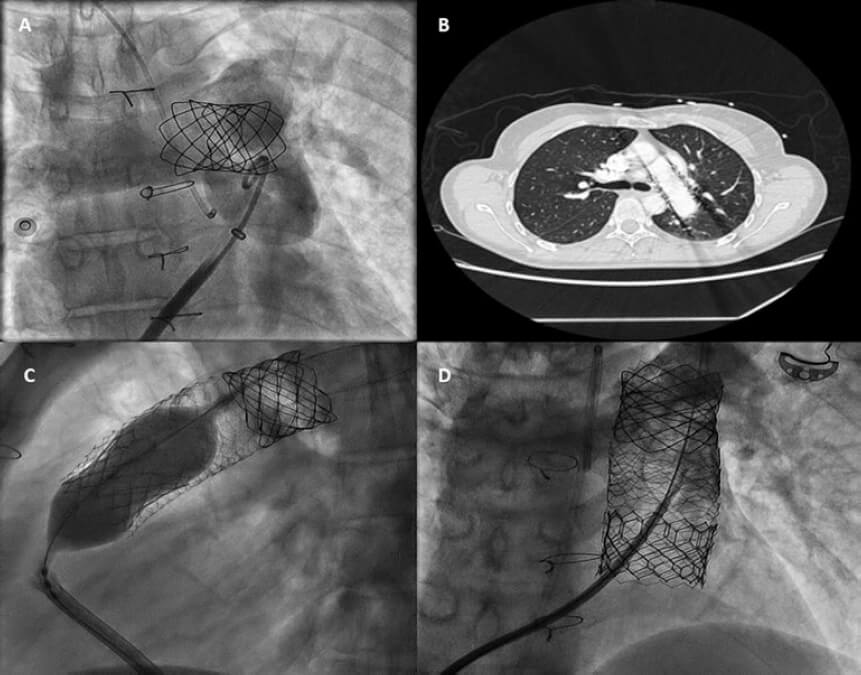

Mujer de 48 años con estenosis pulmonar congénita que precisó una valvuloplastia quirúrgica en 1978 con síntoma de presentación de disnea progresiva. Las imágenes de la resonancia magnética cardiovascular realizada confirmaron la presencia de ventrículo derecho dilatado, insuficiencia grave y aneurisma de arteria pulmonar (39 × 25 mm). El equipo multidisciplinar optó por el implante transcatéter de una válvula pulmonar. Durante la fase previa al implante de un CP Stent no recubierto de 15-25 mm × 47-55 mm (NuMED, Estados Unidos) montado sobre un balón de 25 mm del tracto de salida del ventrículo derecho nativo sobrevino la embolización del stent con anclaje espontáneo a la arteria pulmonar izquierda (vídeo 1 del material adicional y figura 1A). Como la paciente seguía estable, se optó por un manejo expectante que permitiera la endotelización del stent. El stent (figura 1B) se utilizó como sustrato de anclaje con 2 meses de diferencia del implante proximal de 2 stents más largos Andrastent XXL de 57 mm (Andramed, Alemania) montados sobre un balón XL AndraBalloon de 30 x 40 mm para crear una zona de aterrizaje para la válvula Sapien-3 de 29 mm. El resto de la intervención fue todo un éxito (figura 1C). La paciente se mantuvo asintomática y sin defectos de perfusión, tal y como confirmó la gammagrafía pulmonar de ventilación/perfusión y un gradiente transvalvular medio de 7 mmHg sin insuficiencia residual a los 6 meses (figura 1D).

Figura 1.

En casos de tronco pulmonar aneurismático y tracto de salida del ventrículo derecho nativo/no calcificado dilatado, el riesgo alto de migración del stent o de la válvula se puede evitar mediante el implante «programado» de un primer stent de menores dimensiones en una de las ramas pulmonares. Posteriormente, se pueden anclar stents proximales secuenciales a esta zona de aterrizaje para posibilitar la reconstrucción del tronco pulmonar con un riesgo bajo de compromiso del flujo en la rama pulmonar encarcelada. Nuevos estudios para el análisis de este escenario están plenamente justificados.